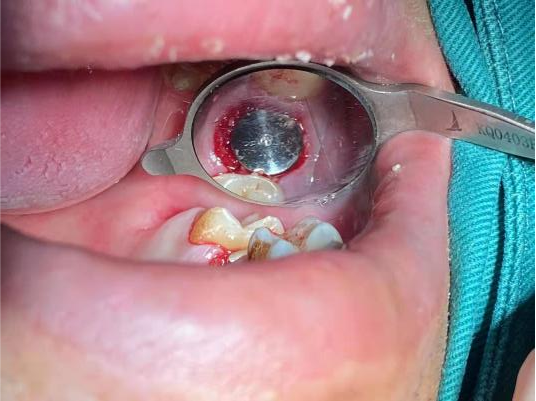

拔除后创口

植体植入